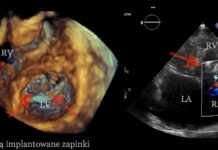

Pierwsza w Polsce pełna, przezskórna korekcja ciężkiej niedomykalności zastawki trójdzielnej metodą brzeg-do-brzegu

W pracowni Hemodynamiki I Katedry i Kliniki Kardiologii WUM przeprowadzono pierwszy w Polsce zabieg małoinwazyjnej, pełnej (tj. dwupłatkowej) korekcji ciężkiej, funkcjonalnej niedomykalności trójdzielnej metodą...